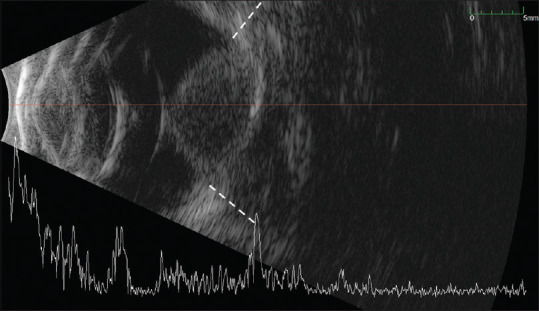

斑块近距离放射治疗在眼内肿瘤的治疗中起着至关重要的作用,允许局部治疗,同时最大限度地减少对周围结构的损害。自20世纪20年代最早报道将缝合的氡种子用于胶质瘤治疗以来,斑块近距离放射治疗在眼肿瘤学领域不断扩大和显著改善。今天,各种各样的眼部疾病,包括肿瘤和非肿瘤,都可以使用斑块近距离治疗。持续的创新也提高了临床安全性和有效性,对提供者和患者都一样。使用新的放射性同位素,结合斑块设计和涂抹器的不断改进以及辐射剂量规划,是一些用于最大化覆盖和减少对关键眼睛结构的辐射暴露的新方法。在本文中,我们将讨论有希望的未来发展,将继续革新治疗。

Plaque brachytherapy plays an essential role in the management of intraocular tumors, allowing localized treatment while minimizing damage to surrounding structures. Since the earliest reports of sutured radon seeds used in glioma treatment in the 1920s, plaque brachytherapy in the field of ocular oncology has continued to expand and improve significantly. Today, a wide variety of ocular conditions, both oncologic and not can be treated using plaque brachytherapy. Continued innovations have also improved clinical safety and efficacy for both providers and patients alike. The use of new radioisotopes, combined with continued refinement in plaque design and applicators alongside radiation dose planning are some of novel methods used to maximize coverage and reduce radiation exposure to critical eye structures. In this paper, we will discuss promising future developments that will continue to revolutionize treatment.